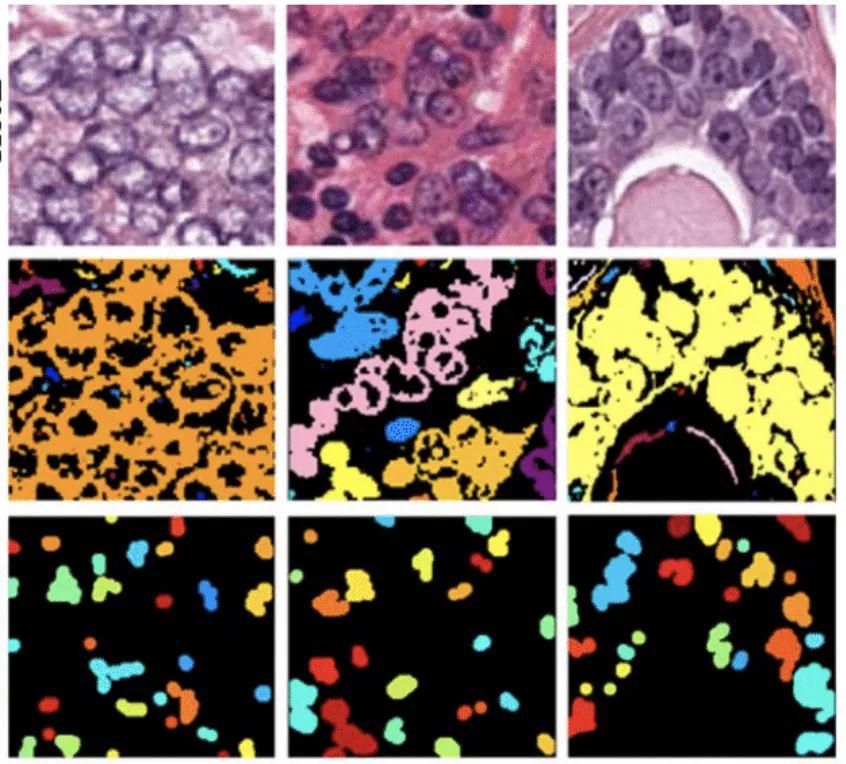

肿瘤数据集

数据集链接:http://m6z.cn/5zCyGj

这一数据集是通过仔细注释几名患有不同器官肿瘤并在多家医院被诊断出的患者的组织图像获得的。该数据集是通过从TCGA存档下载以 40 倍放大倍率捕获的 H&E 染色组织图像创建的。H&E 染色是增强组织切片对比度的常规方案,通常用于肿瘤评估(分级、分期等)。考虑到多个器官和患者的细胞核外观的多样性,以及多家医院采用的丰富染色方案,训练数据集将能够开发出开箱即用的稳健且可推广的细胞核分割技术。

结直肠腺癌组织学图像数据集

数据集链接:http://m6z.cn/6axBLk

该数据集包含 100 张 H&E 染色的结直肠腺癌组织学图像。出于检测目的,在中心/周围共标记了 29,756 个原子核。其中,有 22,444 个细胞核也具有相关的类别标签,即上皮细胞、炎症细胞、成纤维细胞和其他细胞核。